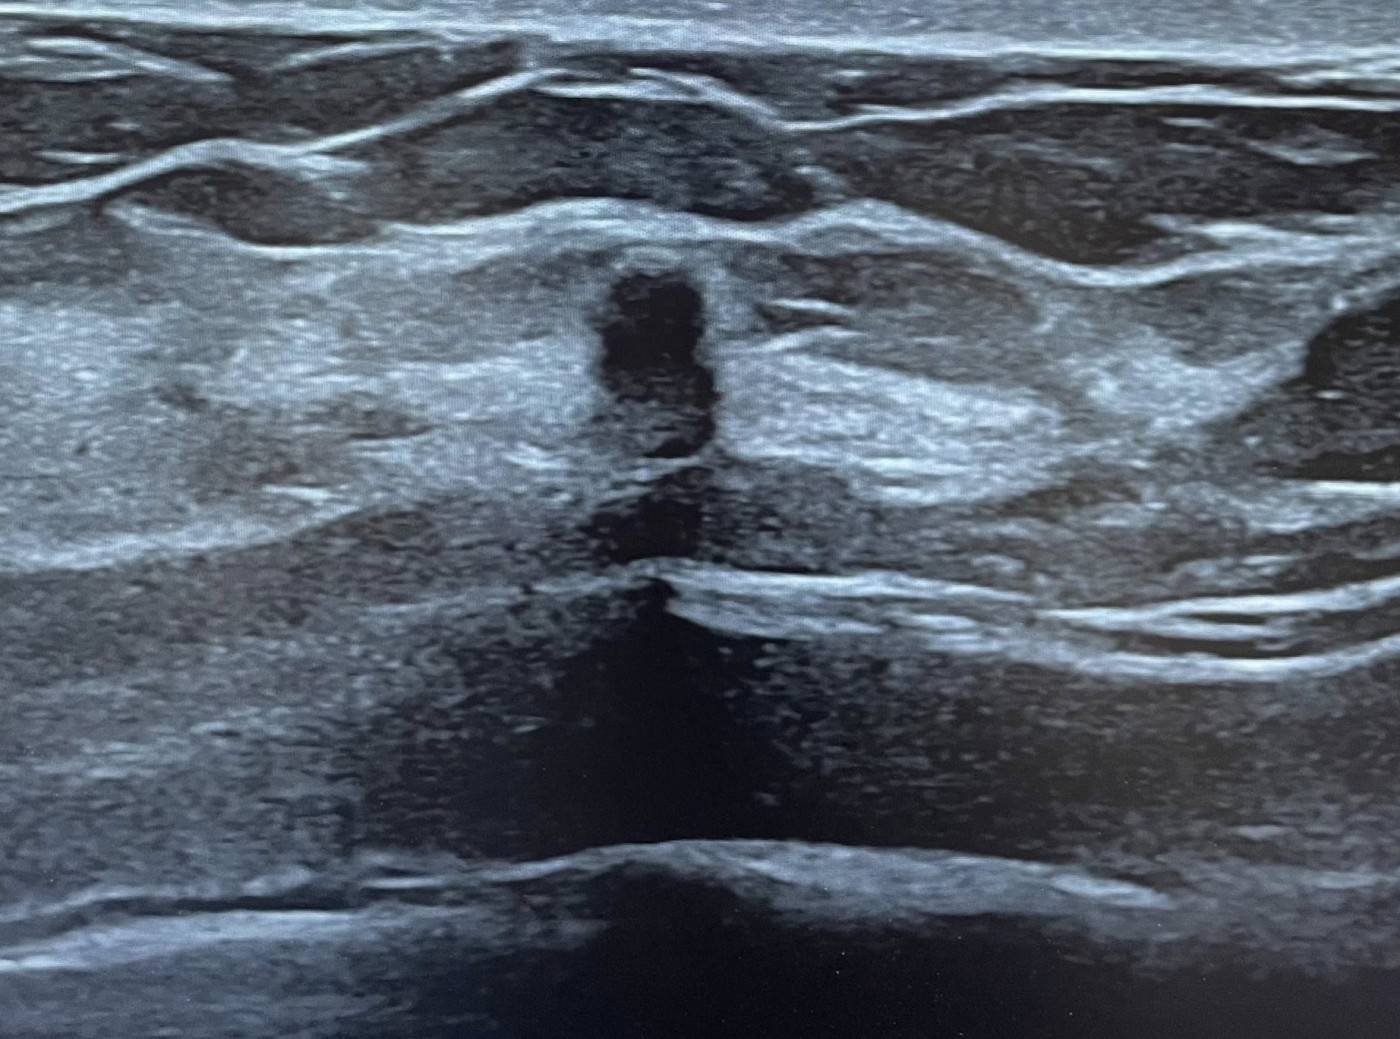

半年後她轉到我門診追蹤,我重新檢視影像後,立刻注意到幾個變化:

- 形狀變得較不規則

- 結構出現非典型特徵

- 最關鍵的是:高大於寬(taller-than-wide)

當腫瘤的生長方向、形狀開始改變,就是需要切片確認的時機。

這位患者雖然腫瘤只有 0.3 公分,但外觀已經出現明顯變化。